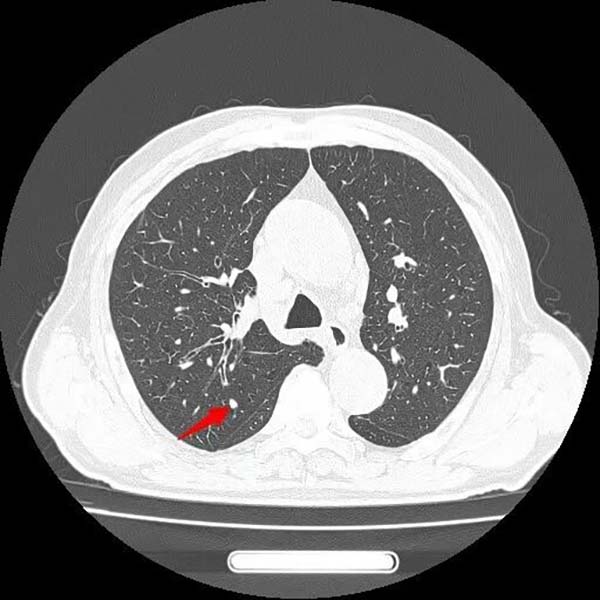

患者王大爷一年前体检发现右肺上叶有一约6×4mm结节,当时未予重视。一年后,他突然出现活动后喘憋症状,复查胸部CT显示右肺上叶后段出现约50×50mm不规则实性团块,影像学高度怀疑肺恶性肿瘤。